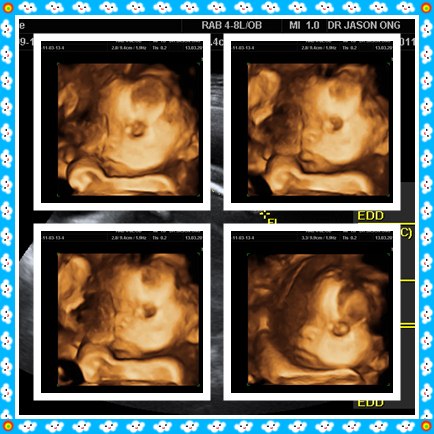

宝宝已经六个月大!^^

是女宝宝哦~^^

找到宝宝的脸型了。。

感觉很奇妙呢。。

好可爱哦^^

她一直在动。。

医生说宝宝很健康!^^

还问我像明星吗?!

医生还真幽默。。